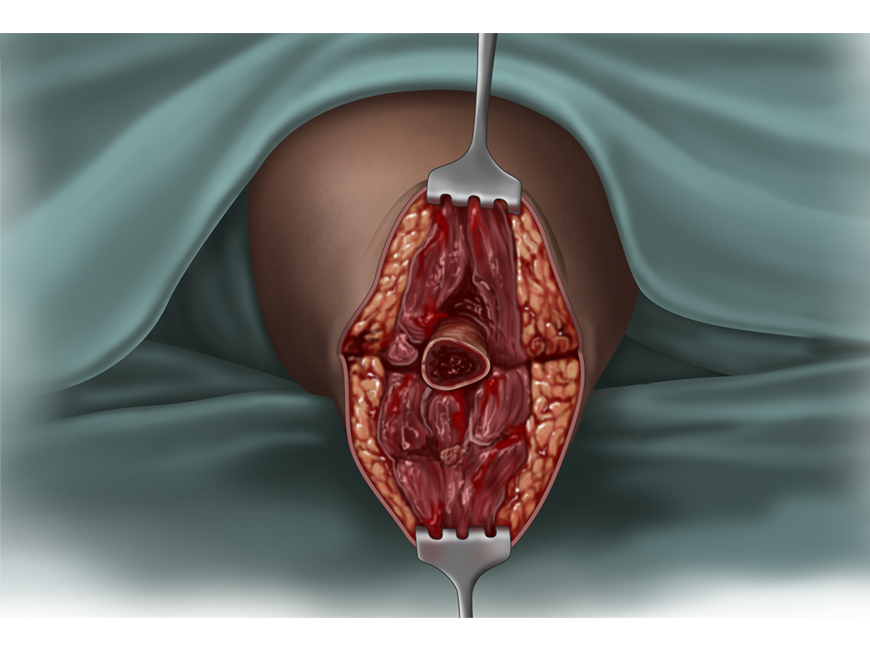

Amputation,

Adobe Photoshop

Courtroom exhibit;

©Kellie Holoski -